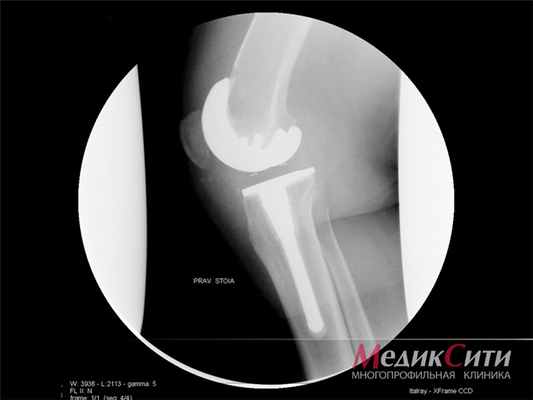

- На границе цемента и кости после артропластики

• Резекция при инфицировании, сдавливании сосудисто-нервного пучка или ограничении объема движений в суставе